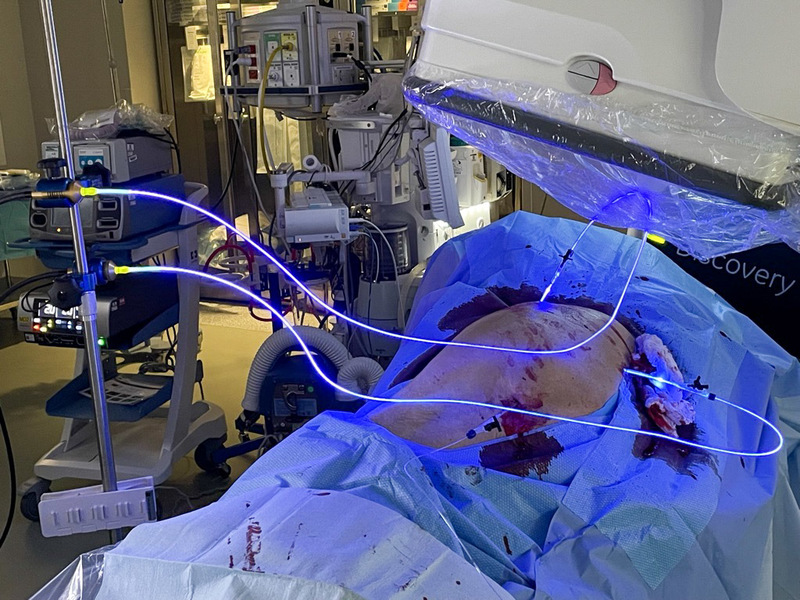

The 63-year-old patient presented with a pathologic acetabulum/hemi-pelvic fracture, and osteolysis with uncontained defect from metastatic lung cancer and additional co-morbidities. The patient has been treated with radiation for metastatic bone disease of the pelvis, and was bed ridden living in a skilled nursing facility due to severe pain and dysfunction resulting from his pathologic pelvis fractures. The patient was brought to surgery and IlluminOss implants were inserted percutaneously through the posterior column, anterior column and LC2 to provide fill and stability for the uncontained osteolytic defect. The implants were filled with a photodynamic liquid monomer and cured with visible blue light. At post-op day 1, the patient was weight bearing as tolerated using a walker. The patient was discharged back to the SNF on post operative day 1 and then from the SNF to home at 2 weeks post procedure. At 6 weeks follow up, patient uses the walker in the community and ambulates unassisted intermittently at home.